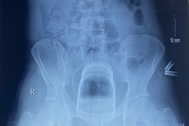

Hình ảnh chụp cắt lớp cho thấy dị vật có kích thước lớn, trơn láng, đang chèn ép trực tràng. Do đặc điểm trơn và lớn, các bác sĩ không thể lấy ra bằng phương pháp nội soi thông thường.